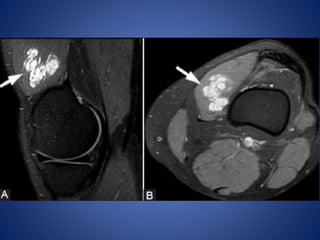

• #35 Intramuscular hemangioma. A 54-year-old female with knee mass and pain. (A) Sagittal T2W fat-saturated and (B) axial T1W fat-saturated post-contrast images show a lobulated enhancing cystic mass (arrows) in the vastus medialis